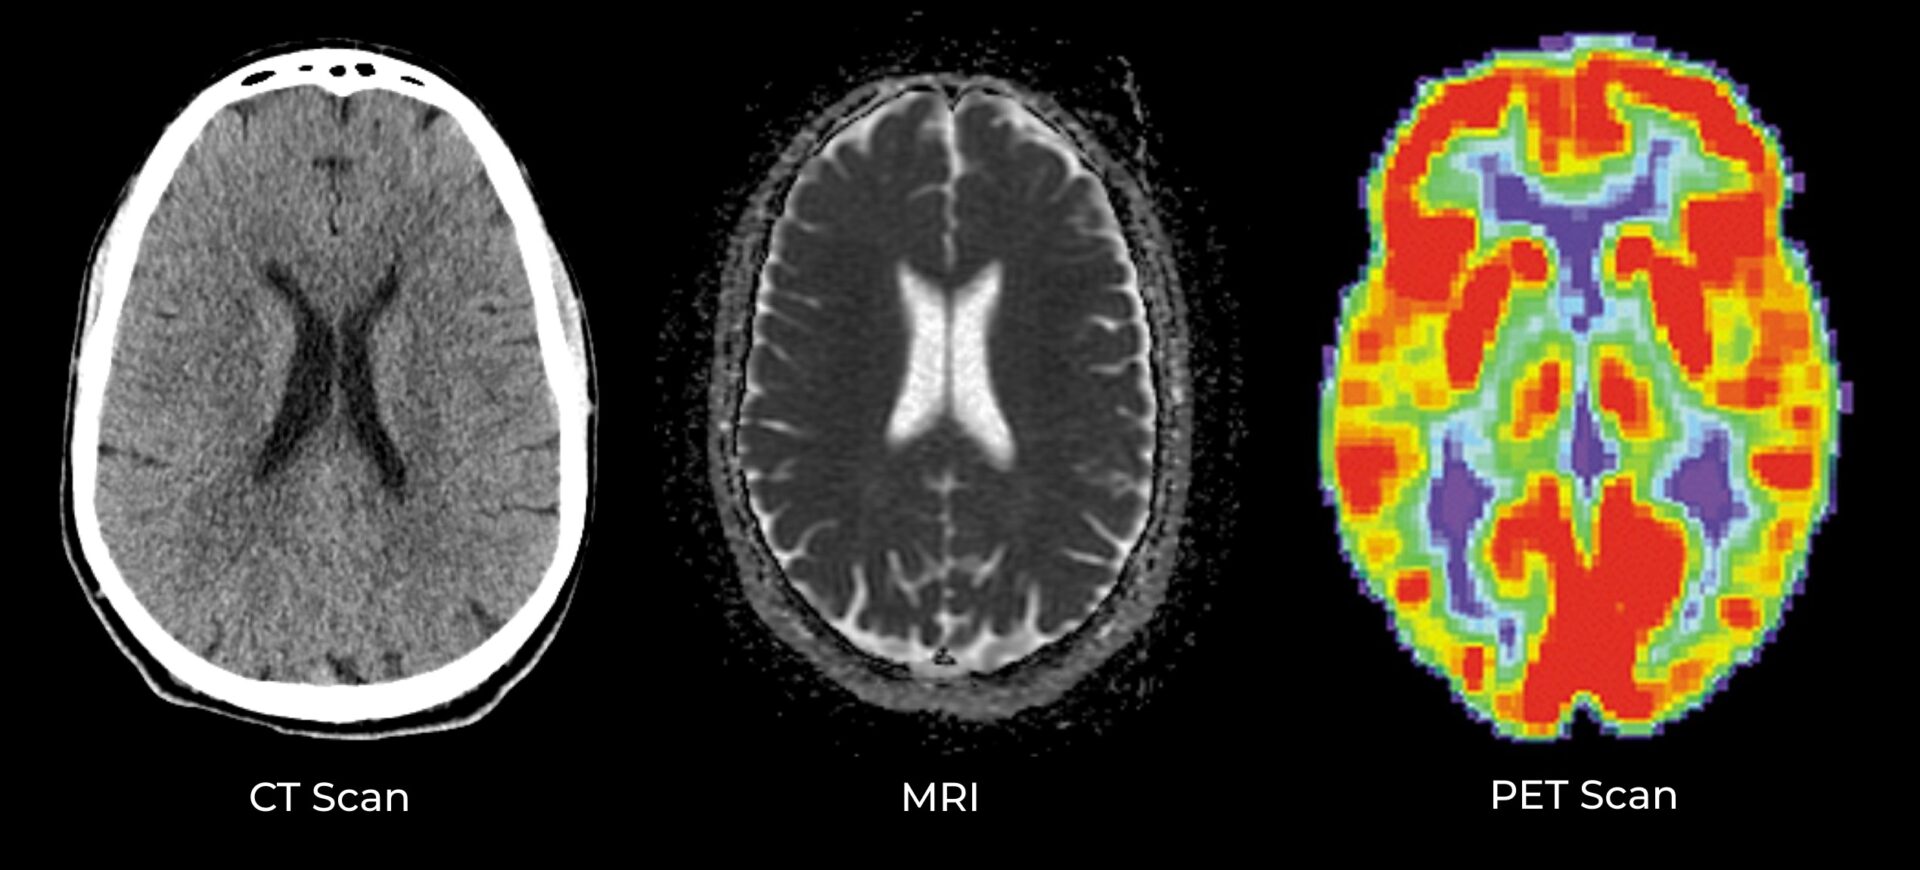

Brain imaging is used to examine the structure of your brain, looking for physical problems such as nerve damage, bleeding, fluid build-up, shrinkage, aneurysm, or a tumor. The two primary types of brain imaging scans are magnetic resonance imaging (MRI) and computed tomography (CT) scans. An MRI is more sensitive and may be done with or without “contrast” (a special intravenous dye that allows the MRI to show blood vessels more clearly and detect where there may be a break in the blood-brain barrier.) A third type of brain imaging is the positron emission tomography (PET) scan. Unlike an MRI or CT scan, which look at the physical structure of your brain, a PET scan looks at how well different parts of your brain are functioning. This is accomplished by injecting a harmless radioactive dye into your bloodstream and watching as it moves through your brain. Like a weather map that shows different temperatures across the country, a PET scan shows different levels of activity in different colors, helping doctors pinpoint which areas of your brain may be under-performing or where there may be abnormal buildups of protein.

Examples of different brain imaging scans - A neuropsychological assessment is a comprehensive evaluation of your cognitive abilities, including your memory, executive function, judgment, attention, and language capabilities. This assessment is typically composed of a variety of tests, administered over several hours. It can be mentally exhausting, but it yields a precise measure of your brain’s output across a wide range of activities.